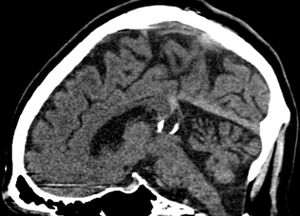

Verkalkte Corpus pineale Zyste sagittal.jpg

Calcified cyst of pineal gland in CT. Sagittal MPR.

كيسة الغدة الصنوبرية pineal gland cyst هو تكيّس حميد (غير خبيث) في الغدة الصنوبرية، a small endocrine gland in the brain. Historically, these fluid-filled bodies appeared on 1-4% of magnetic resonance imaging (MRI) brain scans, but were more frequently diagnosed at death, seen in 4-11% of autopsies.[1] A 2007 study by Pu et al. found a frequency of 23% in brain scans (with a mean diameter of 4.3 mm).[1]